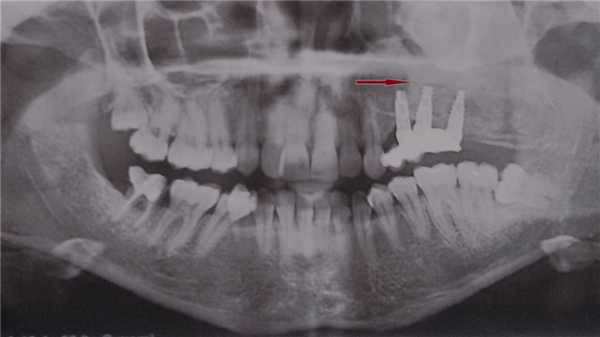

(Справа) На кадрированной панорамной рентгенограмме визуализируется хорошо отграниченный очаг смешанной плотности, который был ошибочно принят за цементобластому, несмотря на наличие выраженной болевой симптоматики и отсутствие фиксации к корню зуба.